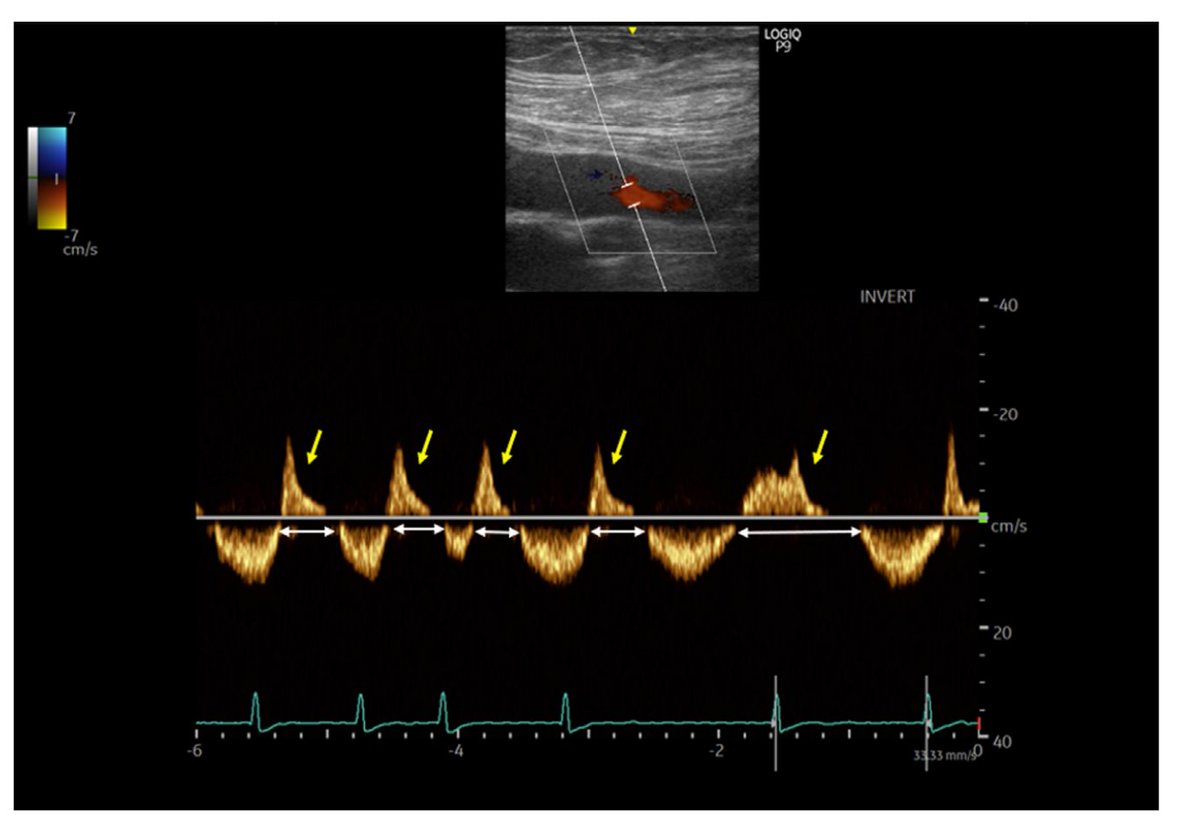

Normal femoral vein flow Doppler for comparison. Note the respiratory modulation and wide monophasic negative vein flow velocity representing antegrade vein flow with minor retrograde vein flow components.

The femoral vein spectral display demonstrates a highly pulsatile waveform with significant flow interruptions (white arrows) and prominent retrograde waves above the baseline (yellow arrows), suggestive of severe venous congestion.